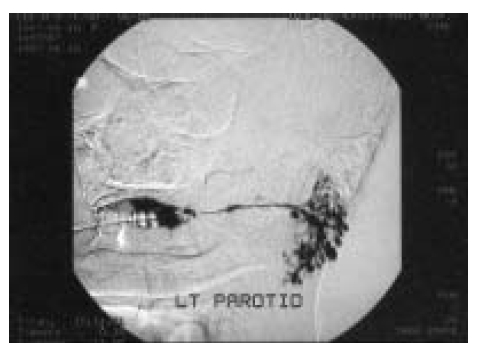

Sialography of salivary gland showed multiple-sized ectatic changes in acina without dilatation and filling defect in the main duct (Figure 2). On biopsy finding of the lower lip, hyperkeratosis and spongiosis were seen, and lymphocytes infiltrated the dermis with exocytosis to the epidermis which was compatible with Sjögren’s syndrome (Figure 3).